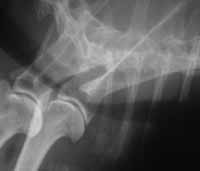

El diagnóstico debe realizarlo siempre un veterinario. Normalmente es preciso llevar a cabo una exploración física completa (para descartar que nuestro perro tenga, además, otras enfermedades), y suele ser necesario un estudio radiológico del cuello y del tórax. En ocasiones, el veterinario realizará un estudio fluoroscópico para observar los movimientos de la tráquea durante la inspiración y espiración. Éste es el método ideal para el diagnóstico puesto que el colapso traqueal no es constante, sino que varía en función de la fase respiratoria. Otras veces el veterinario puede optar por llevar a cabo un estudio endoscópico de la tráquea para visualizar in situ el estado de la membrana dorsal de la tráquea y el grado de alteración traqueal que existe (fotografía 6; Radiografía de tórax donde se aprecia una tráquea normal) (fotografía 7; Radiografía de tórax donde se aprecia un colapso traqueal).